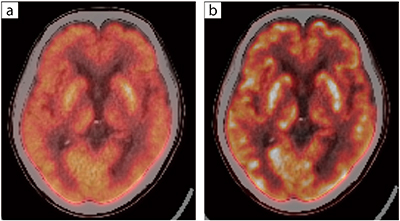

図1 頭部(肺がん検査目的)

a:Conventional(CaLM)

b:AiCE-i

全身条件(2分 / bed)の画像。AiCE-iを用いた画像の方が、脳の皮髄境界を明瞭に描出している。

「AiCE-iでは、CaLMと比べノイズが低減された明瞭な画像を得られます。頭部では皮髄境界が非常に明瞭になりますし、腫瘍も辺縁が明瞭化し浸潤範囲を想定しやすくなります。また、肝臓などの結節においてもCaLMよりもAiCE-iの方がより高いコントラストで観察できます。両画像の特性については、引き続き症例を重ねて比較検討していきます」

また、将来的にアルツハイマー病の治療薬が承認されれば、アミロイドPETのニーズが高まると言われている。福田部長は、「アルツハイマー病の診断において、皮髄境界も明瞭に描出可能なAiCE-iの画質であればアミロイドPETの位置づけが上がるのではないかと思います」と述べ、アミロイドPET用のAiCE-iの開発に期待を寄せた。